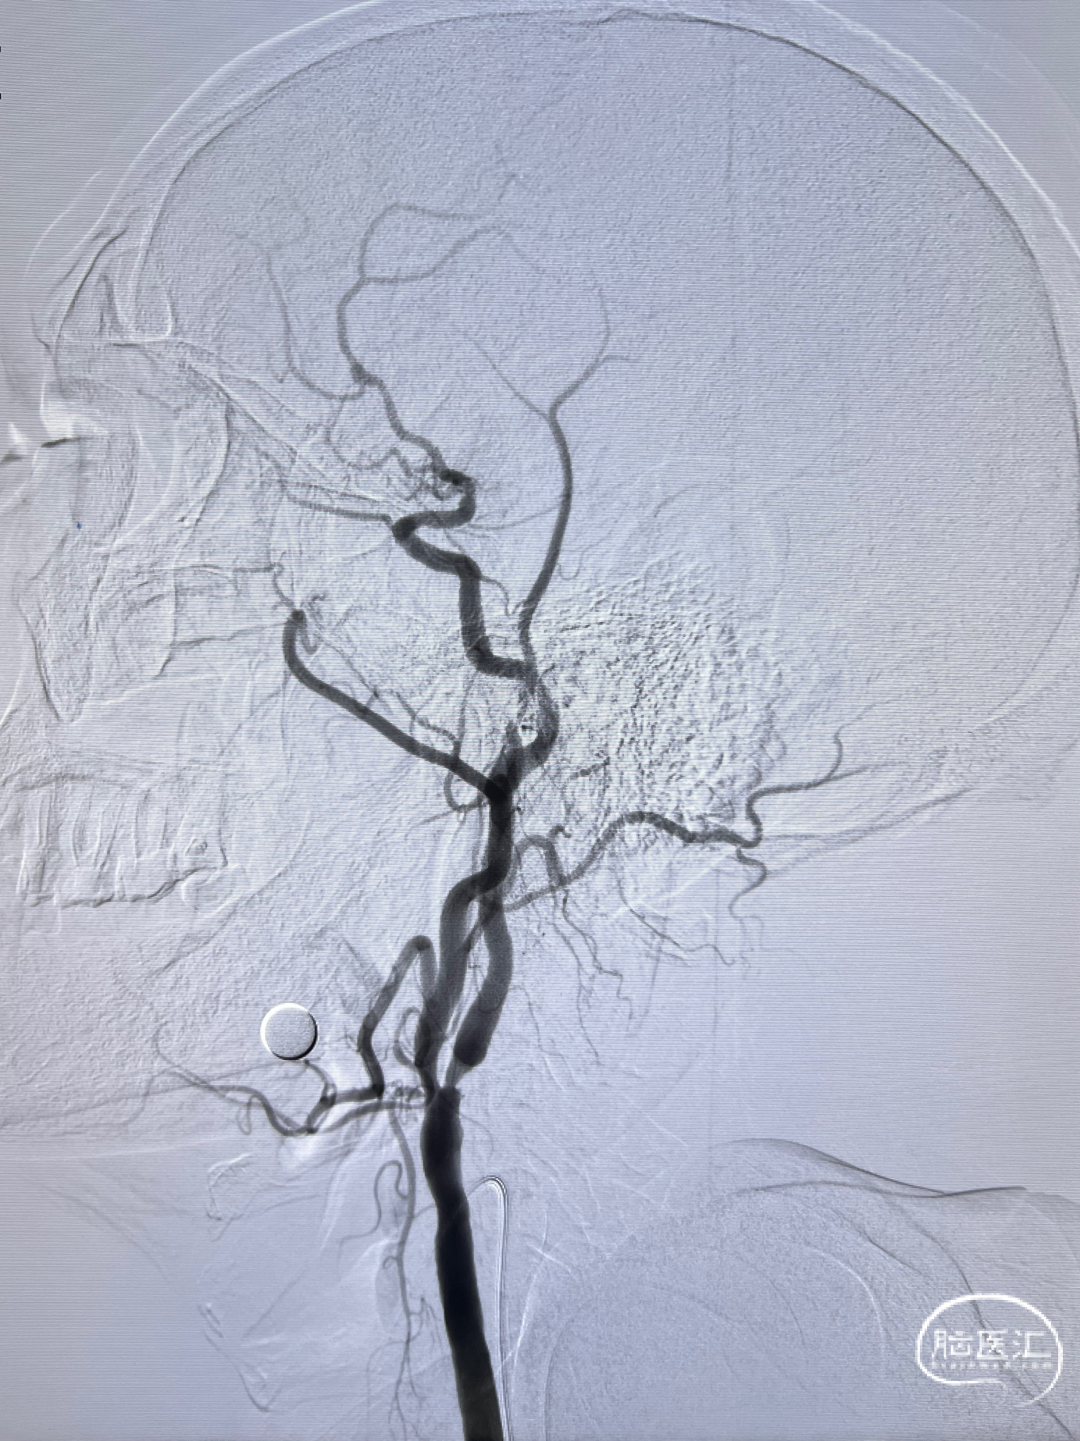

左侧颈内动脉重度狭窄,左侧大脑中动脉闭塞,通过前交通动脉向右侧大脑中动脉供血区代偿。